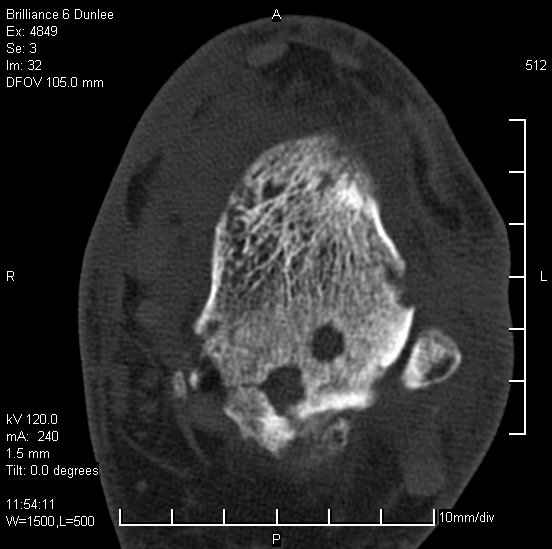

На лечении находится пациент 35 лет. Травма в сентябре 2008 г.- открытый вывих таранной кости

В день травмы ПХО, вправление вывиха, трансартикулярная фиксация. Рана зажила первично. С января нагрузка на конечность. С конца апреля- болевой синдром. На рентгенограммах и КТ признаки ас. некроза таранной кости, артроз подтаранного и голеностопного суставов.